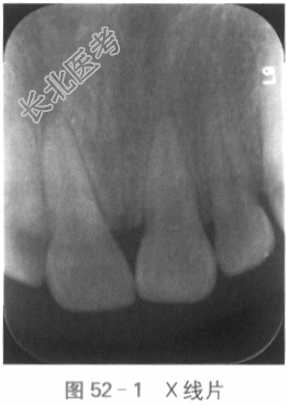

5.辅助检查:X线检查显示:11牙颈部及根方见折裂线,根尖孔基本闭合,牙周膜连续,略增宽(见图52-1)。